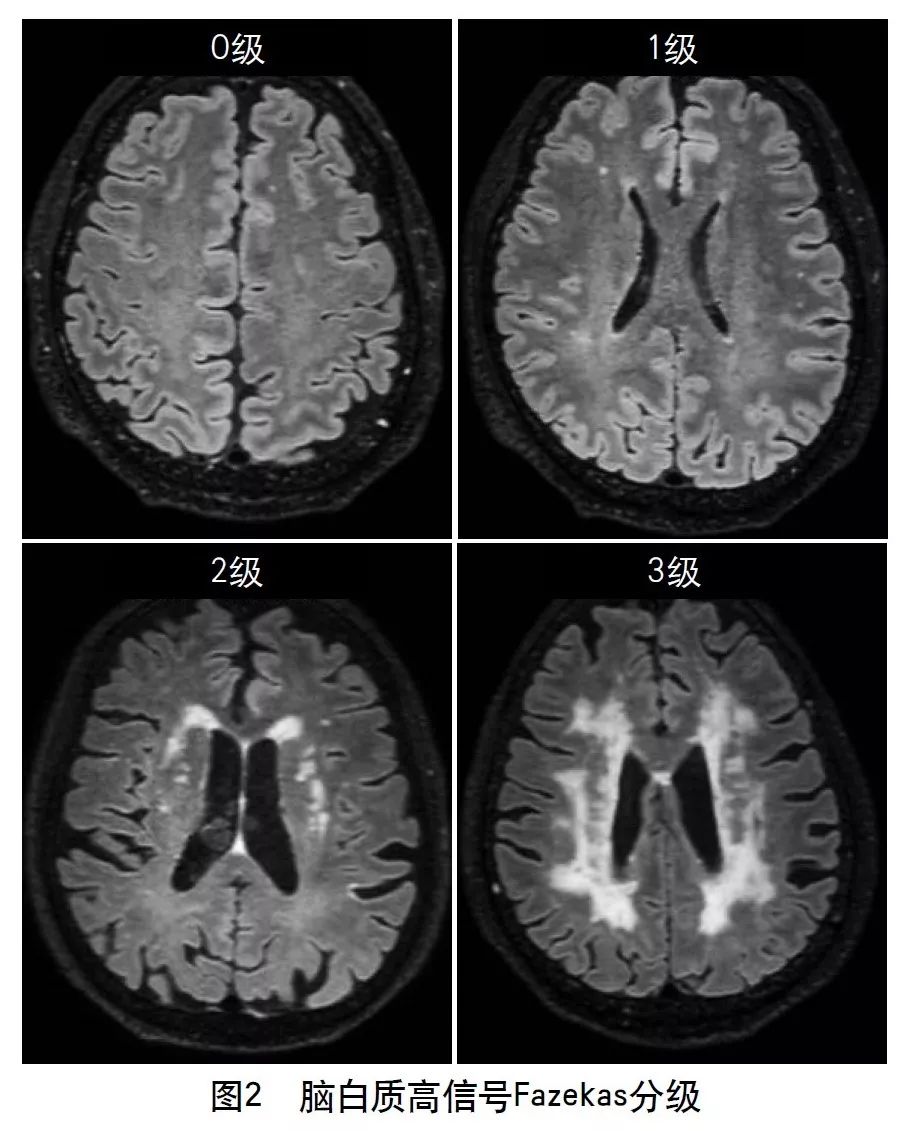

目前对脑白质高信号的影像学评价方法很多,主要有半定量和定量评估。半定量方法主要有Fazekas直观评分量表(图2)、年龄相关脑白质改变(ARWMC)量表、Scheltens量表。其中,Fazekas直观评分量表临床最常用,ARWMC量表可结合病变部位进行分析,能提供更多有效信息。定量方法包括Kropper法和FreeSurfer法,主要利用全自动定量分析软件对扫描后的头颅MRI图像进行分析,通过识别病变区异常信号、勾选病变区、计算病变体积来进行定量分级,从而定量评估白质病变的严重程度。